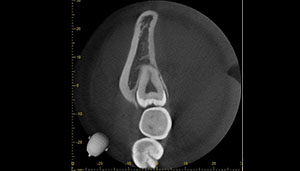

CT

- Before

- After

CTで親知らずと神経(下歯槽管)の位置を確認しました。

親知らずと神経は一定の距離があり、麻痺などのリスクがほとんどないと判断できます。

口腔内

半埋伏の親知らずでした。3糸縫合しました。

| 抜歯内容 | 下顎の親知らずの抜歯希望の患者様です。 智歯周囲炎となっており、初診時では麻酔が効きづらい旨をお話しし、初診時は抗生物質をお出ししました。1週間後、ある程度歯肉の炎症がとれたことを確認して抜歯を行いました。 麻酔を行い、遠心(親知らずの奥側)歯肉と、手前の歯の頬側の歯肉を切開しました。 歯茎を開いて、手前の歯と引っかかっている部分をカットしました。 その後、骨からでている歯冠部(頭の部分)をカットしました。 その後へーベルで歯根(骨に埋まっている部分)を脱臼し、抜歯を終えました。 切開した歯茎を3針縫って、治療終了となりました。 歯茎を切ったため、3日ほど腫れぼったい感じがあったようですが、痛みはほとんどなく、治癒に向かいました。 |